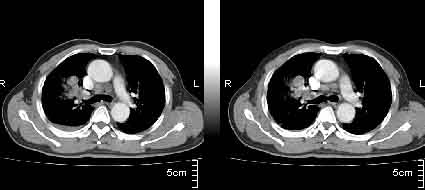

该病例我的诊断意见:右肺上叶周围型肺癌伴纵隔和右肺门淋巴结增大和右肺上叶阻塞性肺炎{病灶周围致密影以近肺门侧明显!}。右侧少量胸腔积液。

一. 1)症状有无发热及慢性过程.2)化验室检查?3)有无tb接触史?二.右肺上叶见片团状影,边界欠清,外侧方见一结节状软组织影,密度欠均匀,内可见低密度坏死区.周围强化明显,肺内见纤维索条影,局部胸膜增厚,但无明确胸膜凹陷.上叶支气管壁增厚,肺门及纵隔淋巴结增大.右侧胸腔少量积液.诊断意见:1右肺上叶慢性感染性疾病(肺tb?)伴肺门,纵隔淋巴结大.右胸少量积液.右肺上叶结节影多为tb球?2右肺上叶周围型肺ca伴肺门,纵隔淋巴结转移待排.右肺上叶炎变(肺门及纵隔淋巴结压迫).右胸少量积液.等待随返结果.

中轴间质增粗可以用癌局部淋巴侵润解释。近肺门侧片影用肺门淋巴结增大解释并压迫支气管引起近端炎症?